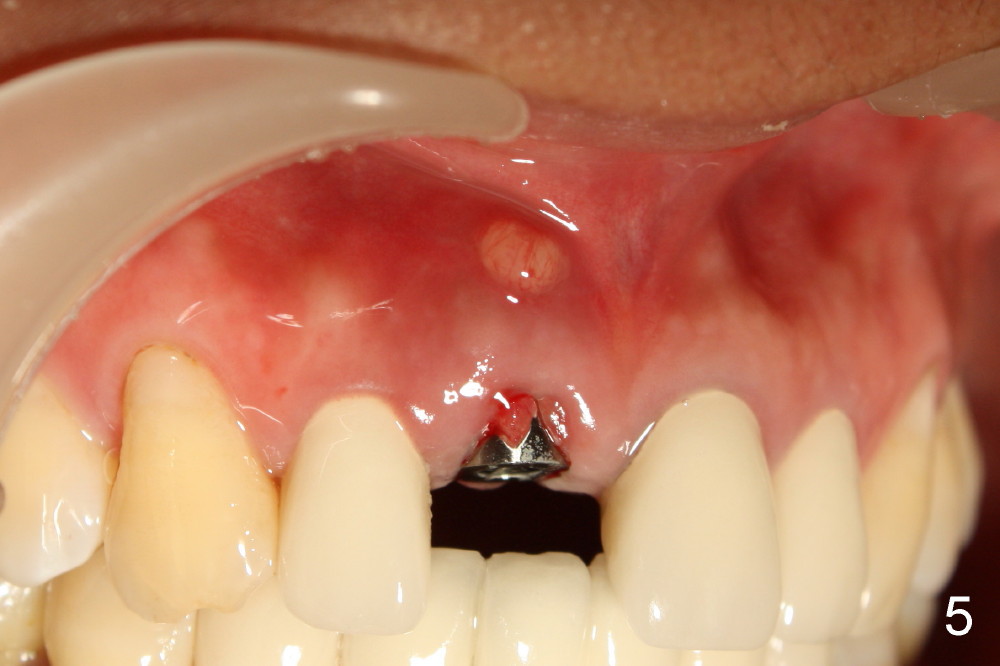

The patient felt better after I & D.  She did not return for irrigation until ten days later (for Christmas).  I & D incision heals.  Swelling and granulation tissue re-appear (Fig.5,6).  In two visits, the implant is stable.

Can we raise flap for more thorough debridement or just remove the implant?